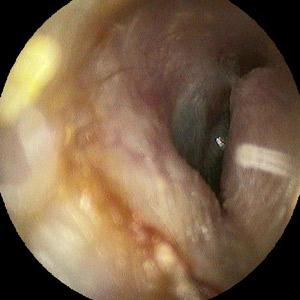

Gehörgangsexostose rechtes Ohr